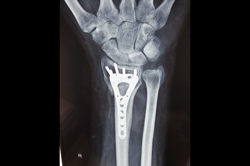

Lower Radius